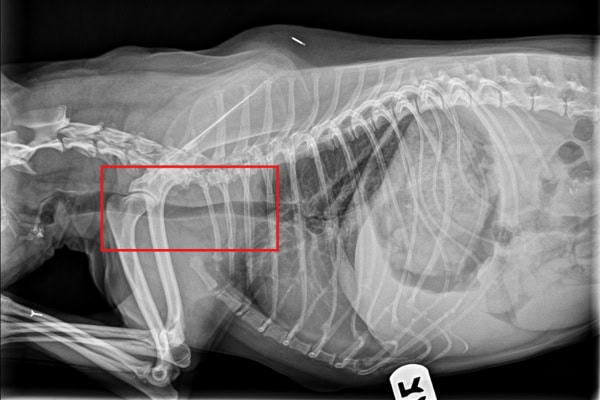

The vet may also run blood tests for dogs to check for signs of infection and evaluate your dog’s overall health. For coughing dogs, taking X-rays to evaluate the shape of the heart, the health of the lungs, and the size and shape of the trachea is very helpful, too. (Note: Tracheal collapse is dynamic, and an X-ray captures one moment in time, so it doesn’t always show up well on X-rays.)